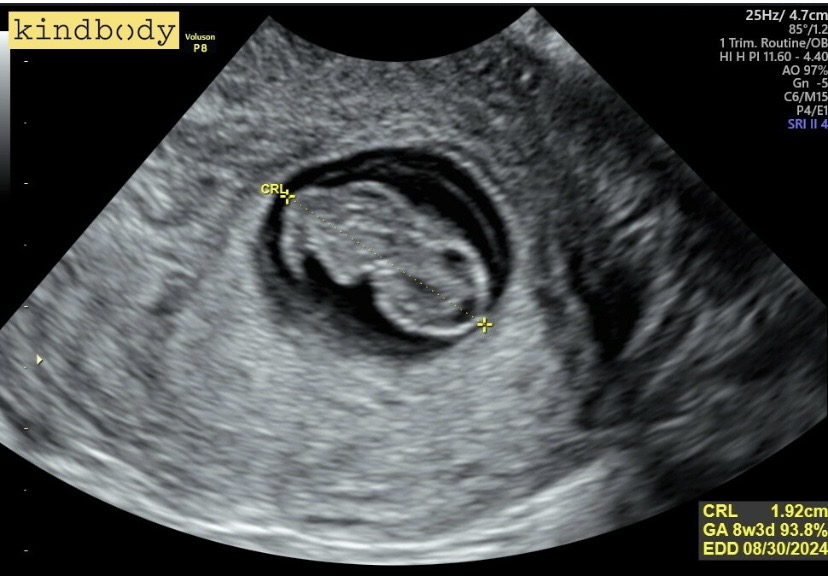

I am 8 weeks pregnant with our baby via IVF! We had been trying for a while with no luck then sought help from KindBody. We did testing, and it turned out IVF was our best shot at baby #2.